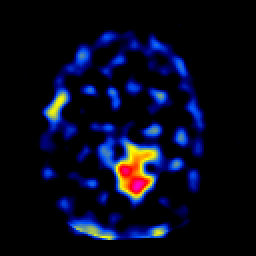

SPECT TL Study #6 -- Slice #33